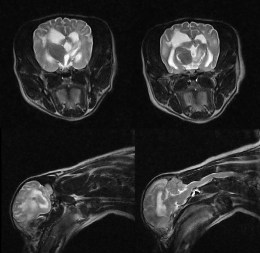

Високодеталізоване МРТ зображення нейрокраніуму собаки в поперечній проекції з чіткою візуалізацією структур мозку